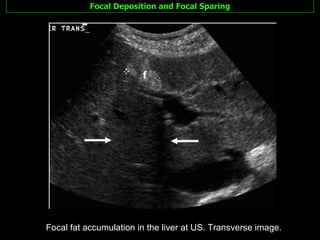

Focal Deposition and Focal Sparing Focal fat accumulation in the liver at US. Transverse image.

Focal Deposition andFocal Sparing Focal fat accumulation in the liver at US. Transverse image.